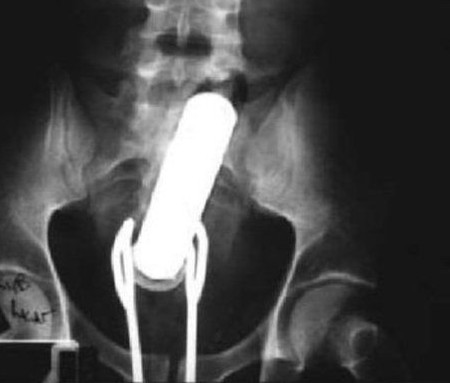

4. Een vibrator en een saladetang

Tsja, als je een vibrator kwijtraakt in je anus dan wil je die er ook graag weer uithalen. Een saladetang lijkt een goed idee, tot die ook vast komt te zitten.